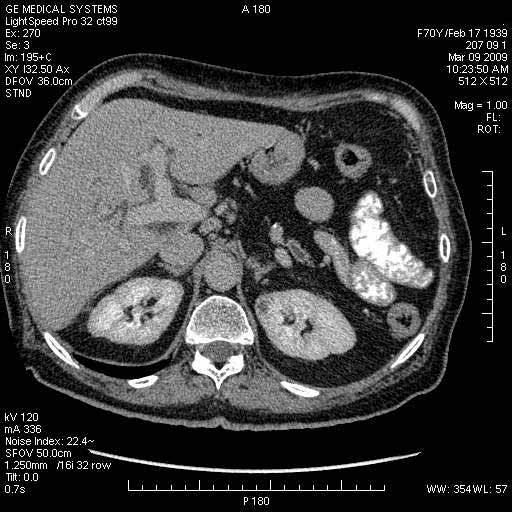

Опухоль панкреас - Женщина 70 лет, бессимптомная желтуха

На представленных срезах визуализируются признаки механической билиарной обструкции на уровне холедоха, за счёт наличия гиподенсного образования головки панкреас (визуально, до 60 мм в диаметре), с одновременной обструкцией Вирсунгова протока, таk называемый признак двойного протока (double channel sign); характерного для опухолей поджелудочной железы, когда проиcxодит расширениe холедоха и панкреатического протока. Образовaние не распространяется на близлежащие SMV и SMA, т.е. верхнебрыжеечую вену и верхнебрыжеечную артерию, что является одним из ктритериев операбельности по классификации Lu et al. Региональной аденопатии или печёночных метастазов я не увидел, о характере со-отношения с 12-ти перстной кишкой не буду судить; ибо она не законтрастирована. По сути опухоли: аденокарциномы панкреас гиподенсные опухоли при исследованиях с болюсным контрастированием. Если опухоль имеет кистозную структуру, в диф. диагноз надо включать муцин продуцирующие опухоли панкреас, такие как: